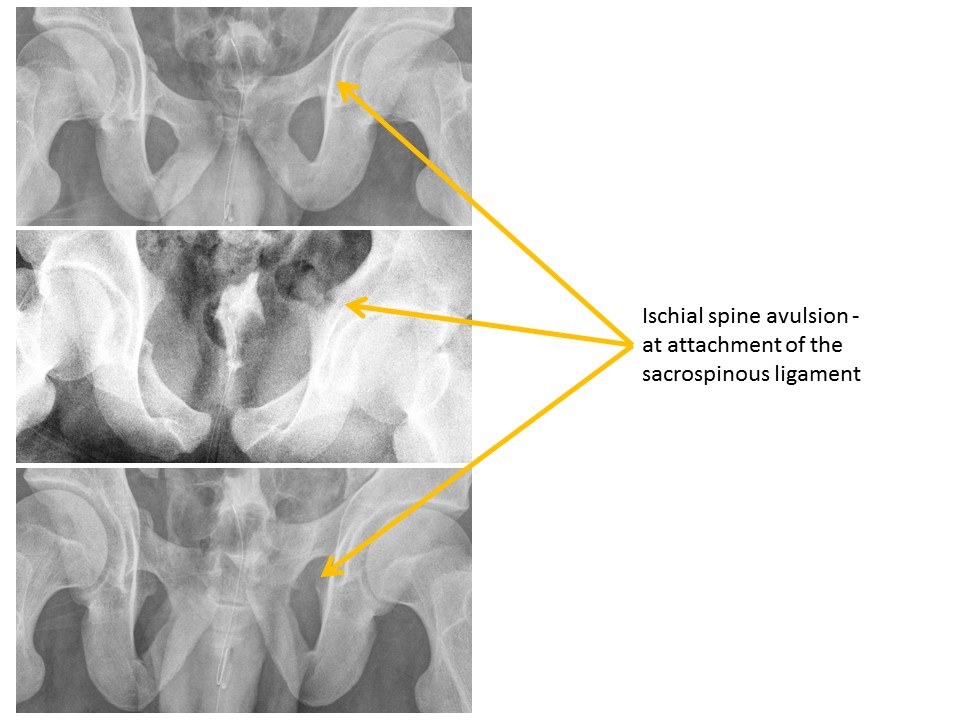

Ischial spine avulsion fractures are present. [Yes/No]